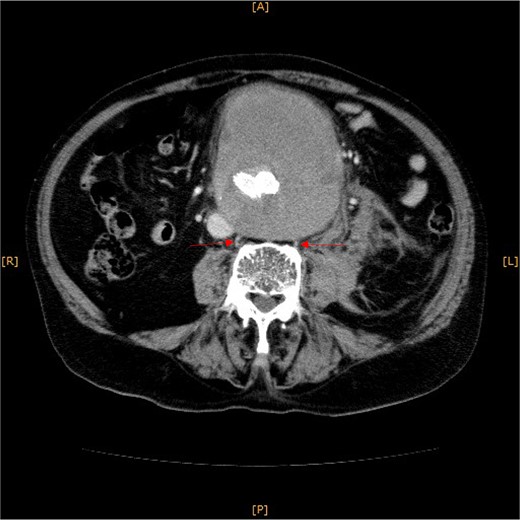

Contrast-enhanced CT revealed an AAA measuring 118 × 107 mm and left retroperitoneal hematoma. One pair of lumbar arteries was enhanced only in the delayed phase (red arrows). Intraoperatively, pulsatile bleeding was observed from the left one of this pair.

This time, he was brought to the emergency department with a chief complaint of abdominal pain. His medical history includes Stage 4–5 chronic kidney disease (CKD), with an estimated glomerular filtration rate (eGFR) of approximately 15 mL/min/1.73 m2, secondary to nephrosclerosis and diabetic nephropathy, as well as persistent atrial fibrillation, which was treated with warfarin. Upon admission, laboratory results revealed a hemoglobin level of 6.2 g/dl and a prothrombin time—international normalized ratio (PT-INR) of 6.05. Contrast-enhanced CT demonstrated an AAA measuring 118 × 107 mm, enlarged from 98 × 94 mm 2 months prior, and left retroperitoneal hematoma. IMA and one pair of lumbar arteries were enhanced only in the delayed phase, but blood flow into the aneurysm was not clearly observed (Fig. 1). Given that the landing zones and overlaps of the stent grafts were satisfactory (Fig. 2) and that no type I or type III endoleaks were identified, a ruptured AAA due to TIIEL from the lumbar artery or IMA was highly suspected. We administered 3000 IU/kg of lyophilized human prothrombin complex concentrate in response to the significant prolongation of PT-INR and proceeded with open surgery for ligation of the feeding artery and aneurysmorrhaphy. Intraoperatively, no pulsation was found on the aneurysm. Incision of the aneurysm revealed a large amount of thrombus, which was removed, and then pulsatile bleeding was identified from a lumbar artery (Fig. 3), the ostium of which was sutured from within the aneurysm. This was consistent with the left lumbar artery of the pair enhanced on the preoperative CT and was suspected to be responsible for the rupture. Oozing was also noted from several other lumbar arteries, which were similarly sutured closed. No leak was observed from the proximal or distal ends, nor from the junctions of the stent grafts, and no damage to the stent grafts was observed (Fig. 4). Following this, aneurysmorrhaphy was performed, and the abdomen was closed. The postoperative course was uneventful. A plain CT on postoperative day (POD) 14 showed a reduction in the aneurysm size with no apparent leaks (Fig. 5). The patient was discharged home on POD 24. Although the preoperative eGFR was 8.8 ml/min/1.73 m2, no postoperative deterioration was observed. It gradually improved back to baseline, and dialysis was not required during the follow-up period.